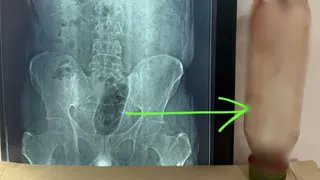

एक्स-रे में हुआ बड़ा खुलासा जब दर्द बर्दाश्त से बाहर हो गया, तो परिजन उसे आनन-फानन में अस्पताल लेकर पहुंचे। डॉक्टरों ने तुरंत उसकी जांच की और एक्स-रे किया। एक्स-रे रिपोर्ट देख डॉक्टर भी दंग रह गए, क्योंकि मलाशय के भीतर बोतल स्पष्ट रूप से फंसी हुई दिखाई दे रही थी।

मामले की गंभीरता को देखते हुए डॉक्टरों की टीम ने तुरंत सर्जरी का फैसला लिया। करीब 36 घंटे की मशक्कत और सर्जरी के बाद डॉक्टरों ने सफलतापूर्वक बोतल को बाहर निकाला।